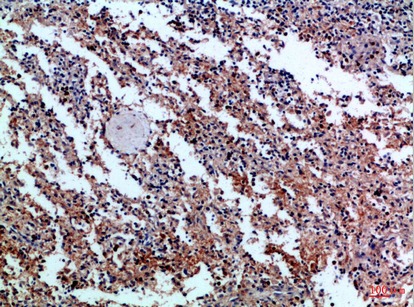

Product Image

TD-P233431.jpg

TD-P233432.jpg

Immunohistochemical analysis of paraffin-embedded Human tonsils using CD42c antibody.High-pressure and temperature Sodium Citrate pH 6.0 was used for antigen retrieval. Immunohistochemistry analysis of paraffin-embedded Human spleen using CD42c antibody.High-pressure and temperature Sodium Citrate pH 6.0 was used for antigen retrieval.